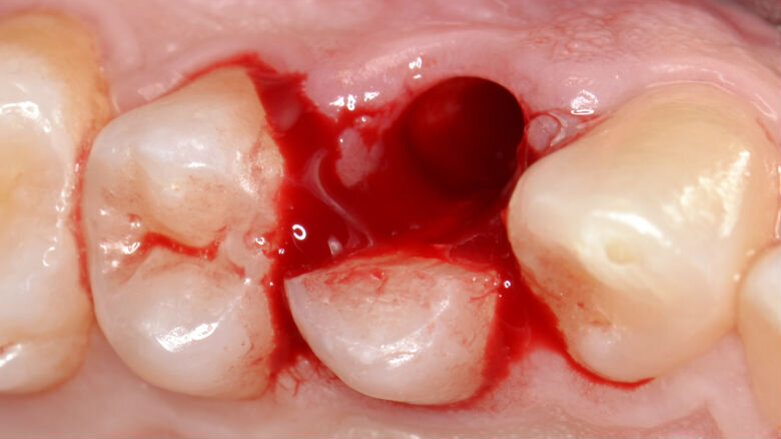

Successivamente, le due parti dell’elemento dentario vengono estratte separatamente avendo l’accortezza di usare estrema cautela nei movimenti di lussazione (Figg. 5, 6). Dopo aver completato la fase estrattiva (Fig. 7) ed aver controllato l’integrità delle pareti alveolari, il tunnel implantare viene preparato mediante l’utilizzo di inserti piezoelettrici dedicati (SUS – Surgery Ultrasonic Site, Esacrom Srl, Imola, Italia) (Fig. 8) con il duplice obiettivo di sfruttare il setto inter-radicolare per garantire una soddisfacente stabilità primaria e inserire l’impianto in posizione protesicamente guidata: una preparazione di tipo tradizionale con frese rotanti esporrebbe infatti al rischio di distruggere completamente il setto osseo che separa la radice buccale da quella palatale, costringendo l’operatore ad abortire la procedura o, in alternativa, a posizionare l’impianto in una delle due radici (Fig. 9).

Fig. 7 - Alveolo postestrattivo integro.